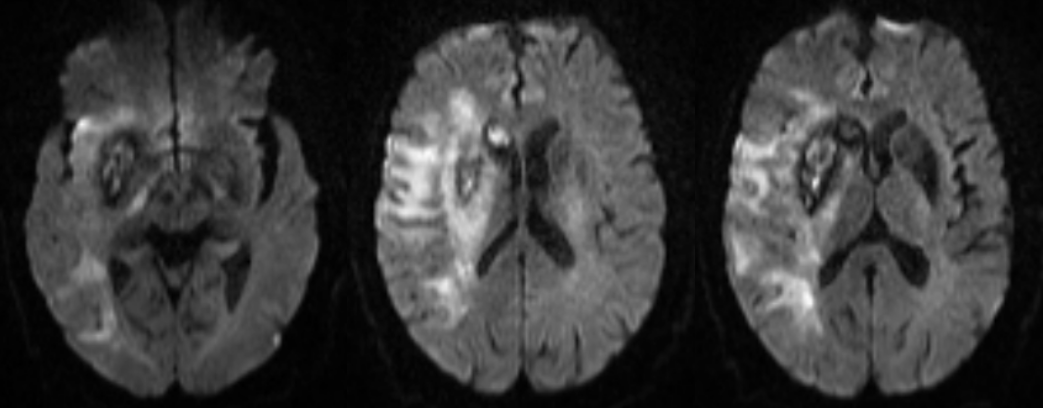

辅助检查

右侧颈内动脉造影显示右侧颈内动脉闭塞。

侧枝代偿差。

选择4.0×20mm支架,采用swim技术取栓2次,取出少量暗红色血栓,颈动脉造影未见血流恢复,单支架取栓无效。

考虑血栓负荷量大,遂采用双支架取栓技术。

梗死合并少量出血,暂不给与抗凝抗血小板药物,给与脱水、营养神经、清除脑自由基、改善循环、补液营养支持以及抗感染等药物治疗。

术后5月复查CTA显示右侧颈内动脉及大脑中血流通畅。